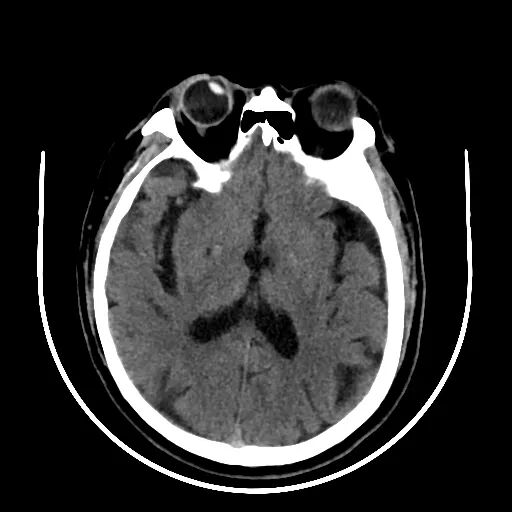

术后颅脑CT无出血: